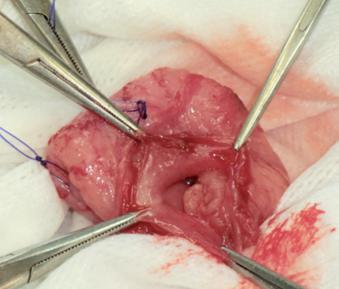

尿管結石

尿管切開による結石摘出